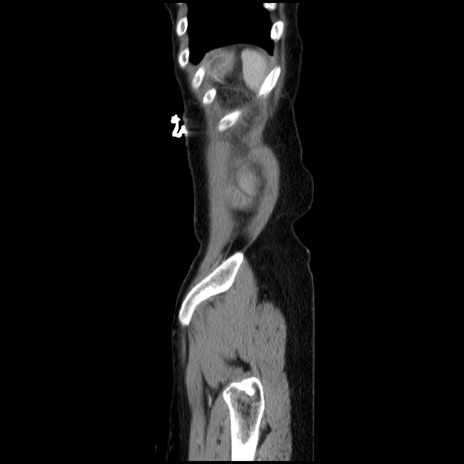

症例32(矢状断像)

【症例】40歳代 女性

【主訴】上腹部痛、嘔気・嘔吐

【現病歴】約9時間前頃から急に上腹部痛、嘔気、嘔吐が出現。改善しないため救急要請。

【既往歴】子宮頚癌(広汎子宮全摘術、放射線療法)、腸閉塞

【身体所見】腹部:平坦、軟、腸雑音亢進、上腹部を中心に腹部全体に圧痛あり。

【データ】WBC 8400、CRP 0.03